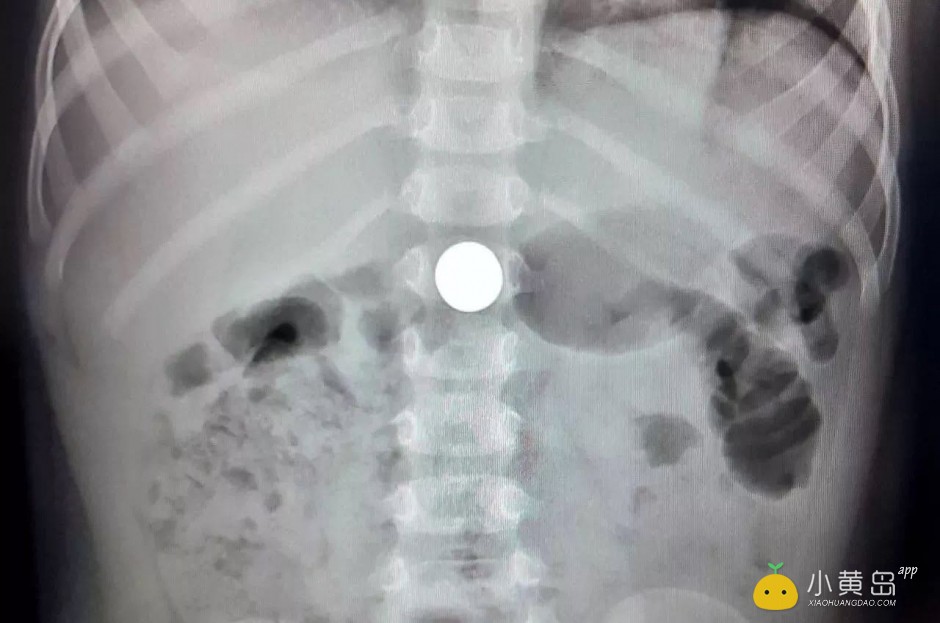

人民日报曾公布了一组图片,小孩子误食的东西五花八门:纽扣电池、玩具配件、钉子、玻璃弹珠、硬币......

WechatIMG479.jpeg